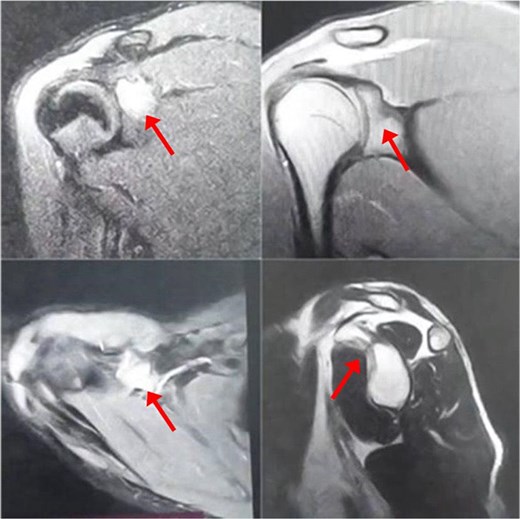

The patient initially underwent conservative treatment with NSAIDs and rest, but symptoms did not improve. As a result, surgical intervention was planned using the deltopectoral approach. The procedure begins with the patient positioned in the beach chair position under general anesthesia. A longitudinal incision is made along the deltopectoral groove, and the cephalic vein is identified and retracted laterally with the deltoid. The deltoid is retracted laterally and the pectoralis major medially to expose the clavipectoral fascia, which is incised to access the coracoid process. Blunt dissection is used to expose the base of the coracoid while avoiding neurovascular structures. Decortication of the coracoid base is performed, followed by biopsy of the lesion (Fig. 3a) and fixation of the coracoid process with a screw (Fig. 3b). An X-ray was performed postoperatively to confirm proper placement of the screw (Fig. 4).

Multiple fragments of tan and bony tissue measuring in aggregate 2 × 1.5 cm taken from the base of the coracoid process (a). Intraoperatively, fixation of the coracoid process with a screw (b).